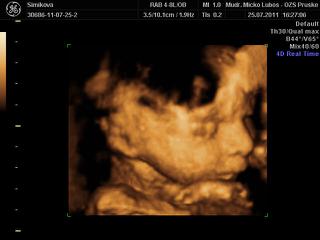

dnes som sa objednala na 3D do hlohovca, som strasne zvedava a nedockava co cakame, hned mi dali termin 9cakala som , ze budem 3tyz cakat), ale ideme uz vo stvrtok. Som zvedava, niako niesom nadcena 3Dckami, sa mi foto deticiek nepaci, take stlacene kadejake.... ani s malym som nebola, ale u neho som vedela, ze chlapec to bude, no tento pocit, ze neviem ma nici, nic si nemozem chystat 😝